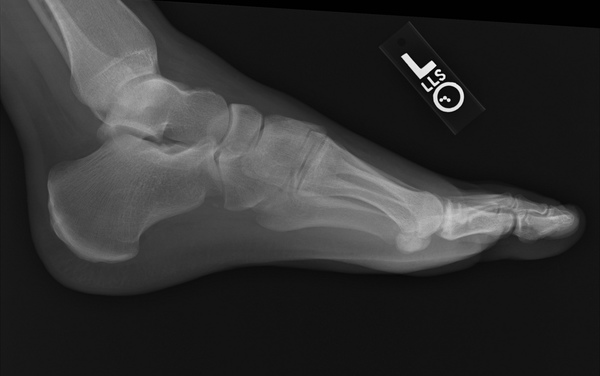

Bir ayağınızda ya da her iki ayağınızda da kronik ağrı hissediyorsanız bunun nedeni topuk dikeni olabilir. Kulağa korkutucu gelse de tedavi edilebilir.

Dr. Donald DeFabio, topuk dikeninden kurtulmanın kolay olduğunu ifade ediyor. Topuk dikeni, ayağınızı aşırı acıtır. Kendiliğinden geçmesi ise bir yılı bulabilir.

Uzun bir süre aynı yerde oturduktan sonra veya sabahları kalktığınızda acısını daha fazla hissedersiniz. Topuk dikeni, aslında topuk kemiğinin alt kısmında diken benzeri bir çıkıntıya verilen addır.